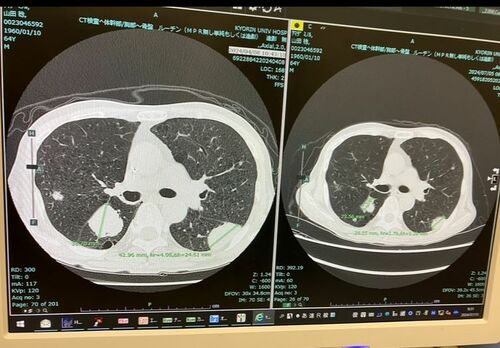

まだまだ暑い日が続いていたが、暦はすっかり秋になっていた。9月30日、病院で血液検査とCT撮影を行った。結果は、残念なものだった。前回(7月)よりも肺の腫瘍が、わずかではあるが大きくなっていたのだ。期待して臨んだ「がん免疫療法」だったが、効果は見られなかった。